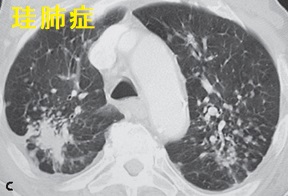

珪肺症

珪肺では肺の炎症に加え、肺門部、縦隔の石灰化を伴うリンパ節腫大が生じます。甲状腺癌の肺への転移リンパ節も石灰化を伴い、鑑別が必要です。実際に甲状腺癌の転移リンパ節と珪肺の炎症性リンパ節が混在した報告があります。(Auris Nasus Larynx. 2020 Dec;47(6):1054-1057.)

珪肺症胸部X線;通常は肺上野の多発する1~3mmの円形陰影

珪肺症胸部CT